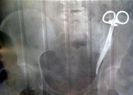

A Woman Had Surgical Clamp Lodged In Her Abdomen For 23 Years!

Misplacing instruments in the body during surgeries is a regular scene where the patients tend to suffer from chronic pain and illness for years until the real reason is found out. According to a survey, in one in 30 cases, surgeons ...